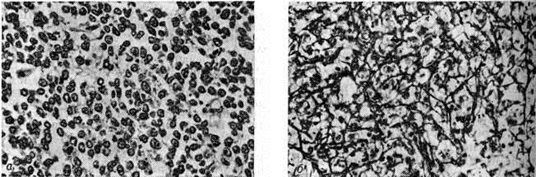

Микроскопически основным структурным элементом являются опухолевые клетки лимфоидно-ретикулярного типа с более или менее выраженными признаками полиморфизма и атипии с овальными, бобовидными или подковообразными ядрами и достаточно чётко контурированной цитоплазмой (рисунок 1, а), Клетки Ретикулосаркома кости первичная по размерам несколько крупнее клеток саркомы Юинга (смотри полный свод знаний: Юинга опухоль). Иногда клетки содержат два или три ядра, обычно с хроматином в виде грубых неправильной формы глыбок. Часто наблюдаются фигуры митоза.

В отличие от опухоли Юинга в Ретикулосаркома кости первичная почти постоянно удаётся выявить богатую сеть аргентофильных волокон, которые иногда оплетают почти каждую клетку (рисунок 1, б), В цитоплазме клеток Ретикулосаркома кости первичная не содержится гликоген. В периферических отделах опухоли часто наблюдаются признаки коллагенообразования иногда вплоть до формирования небольших фиброзных полей. В этих же участках опухоли можно видеть и очаги реактивного остеогенеза.

Рис. 1.

Микропрепараты первичной ретикулосаркомы кости: а — все поле зрения занято опухолевыми клетками с выраженным атипизмом; окраска гематоксилин-эозином, ×250; б — видна сеть аргентофильных волокон, оплетающих опухолевые клетки; импрегнация серебром, ×250.